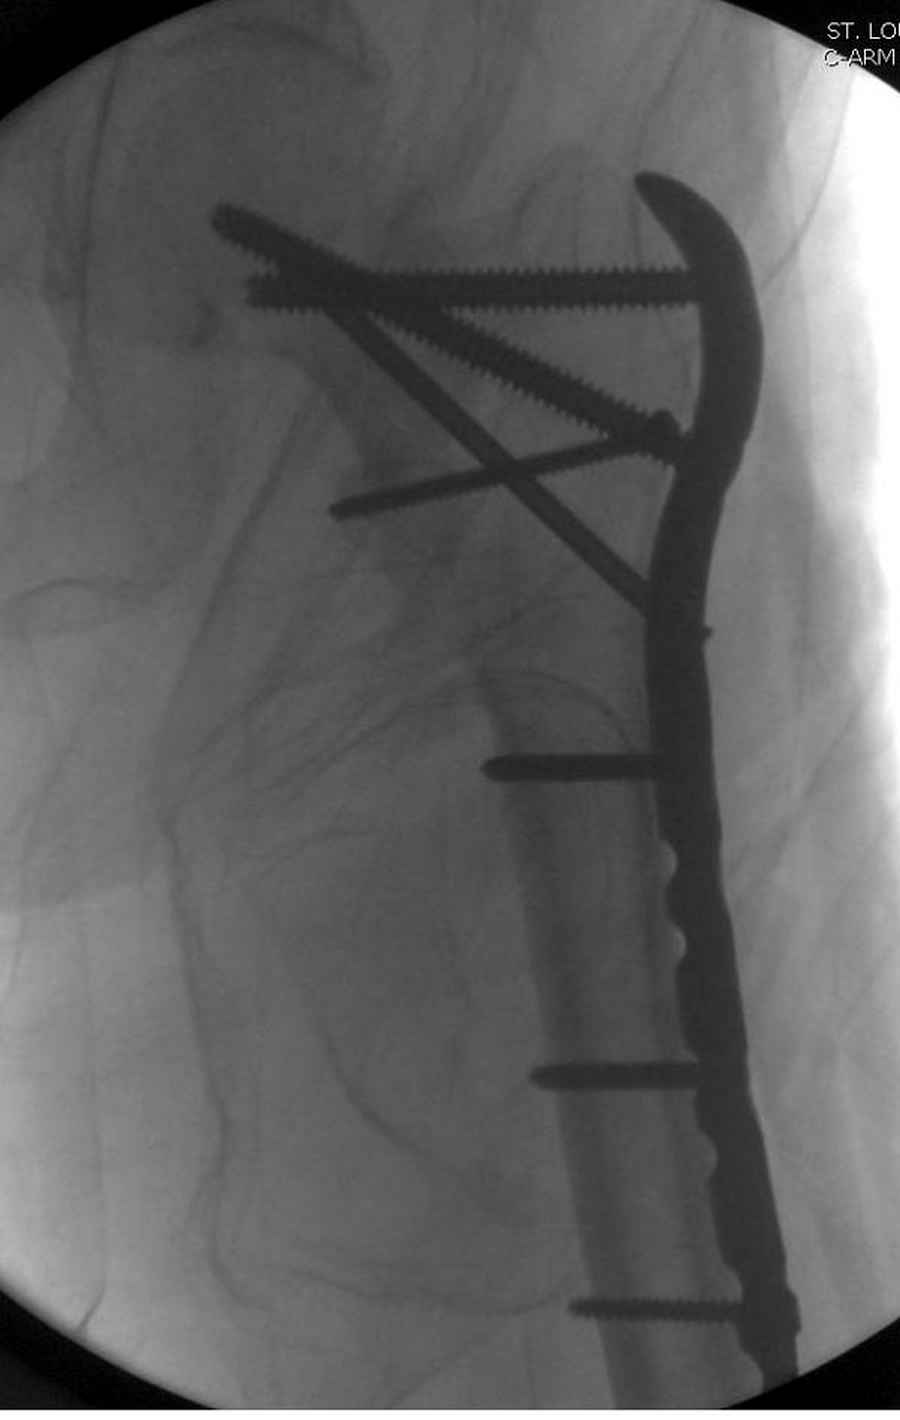

Здесь 83 года, травма в результате падения

судя по картинкам с ЭОПа явно использовались приемы непрямой репозиции под его контролем, а так же интраоперационный ЭОП-контроль положения винтов, без такого контроля операция может ухудшить ситуацию (опять же учтите сроки) т.к. результат буде зависеть в большей степени от искусства хирурга, а не от технологии